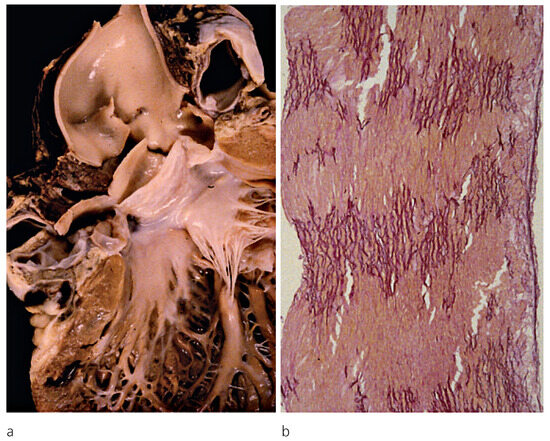

Up to ten percent of acute coronary syndromes occur during or shortly after physical exercise. In fact, physical exertion of more than 4 METs transiently increases the risk for myocardial infarction which remains elevated until an hour afterwards. Th...